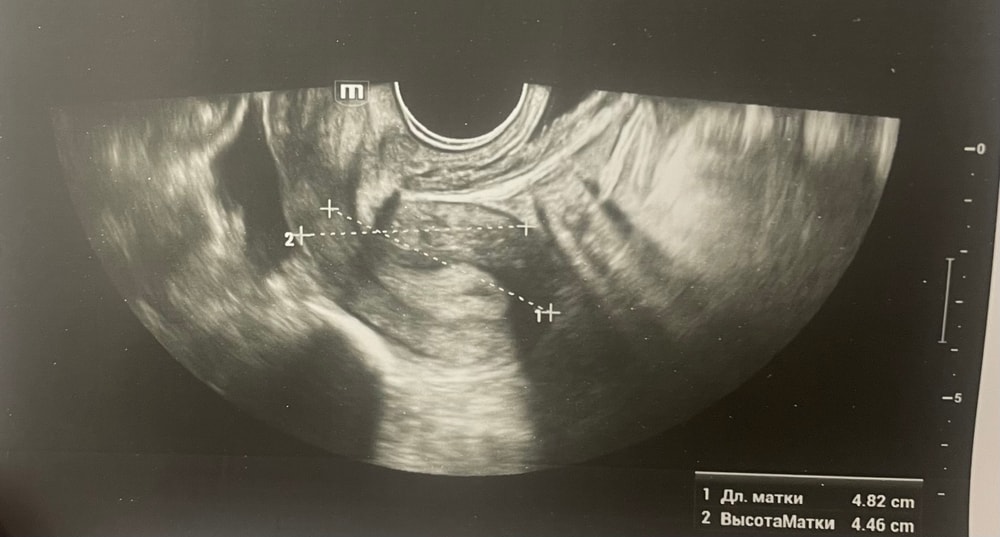

Прошу советаДобрый день, мы с мужем планируем беременность и в этом месяце произошло что то странное… дата начала последней менструации 4 октября закончилась 8, овуляцию отслеживала всю неделю почти сначала были бледные еле заметные полоски, 23 октября жирные четкие полоски, 24 октября стала чуть бледнее но яркая, вообщем положительный ещё был, с 25 числа тест уже отрицательный, через день после овуляции 26 числа стала странно себя чувствовать и во время овуляции болел живот то справа то с лева и поясница, так через день после начали болеть соски грудь вообще не болела, живот то болит то нет и с поясницей также, позже появилась небольшая изжога, нога немеет правая не знаю с чем связано), все это началось за 2 недели до месячных в середине цикла скажем так 29 числа пошла на узи спустя 6 дней грубо говоря гиня сказала что у меня была очень хорошая овуляция, что её признаки сохраняются до сих пор так скажем, желтое тело СПРАВО 20 мм, мои симптомы и все это очень похоже на беременность сказали большая вероятность, я очень была рада и надеялась, после узи появились выделения с комочками, до этого были просто густые белые выделения, утром тоже самое, пошла опять к гинекологу она сказала это может быть при ранец беременности сказала какие свечи купить, вечером я попала в не большое ДТП, удар был в поясницу и копчик, живот начал тянуть и поясница сильно болеть, начала болеть сама грудь помимо сосков, живот прошел относительно быстро, а вот поясница ломит до сих пор, решила сходить ещё раз на узи очень испугалась, на узи я пошла 31 через два дня после предыдущего и уже к другому гинекологу, моя на больничном, она сказала, что у меня отсутствуют даже косвенные признаки беременности и желтое тело с ЛЕВО А НЕ С ПРАВО, я не понимаю как такое может быть, очень расстроилась и совсем забыла про фото узи, она мне его не дала только заключение и как выяснилось уже не дадут оно не сохранилось, сказали переделывать, я очень доверяю своему гинекологу, но по заключению второго врача о беременности не может быть и речи в этом цикле, я не понимаю как желтое тело оказалось с лево если оно точно было справа в этом я уверена, а вторая врач уверяет во Братном, живот в обуляцию хоть и болел с двух сторон но больше справа помойму, вообщем я не понимаю есть ли шанс что я беременна или все таки нет, я понимаю что это слишком рано, до задержки ещё 4 дня, но мне плохо уже неделю по симптомам даже больше это же не просто так, я прикреплю фото заключения, могу ли я быть беременна, если посмотреть на эти заключения хотябы, подскажите пожалуйста фото узи относятся к 29.10, без фото 31.10